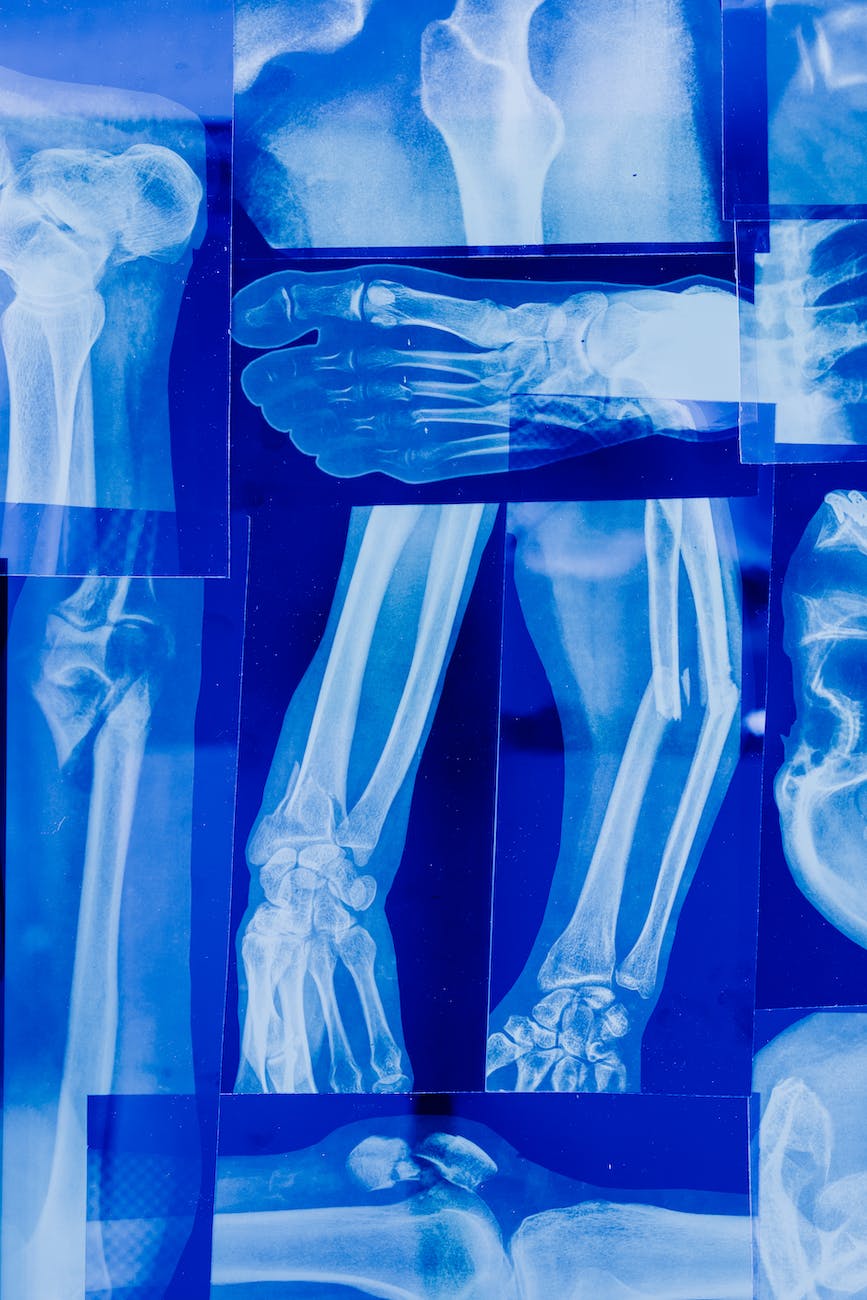

Los rayos X son una forma de radiación electromagnética que se utilizan para obtener imágenes de los huesos, los órganos y otros tejidos del cuerpo. Aunque los rayos X son una herramienta útil para diagnosticar y tratar muchas afecciones médicas, es importante tener en cuenta que también pueden ser perjudiciales para la salud si se exponen a ellos de manera inadecuada.